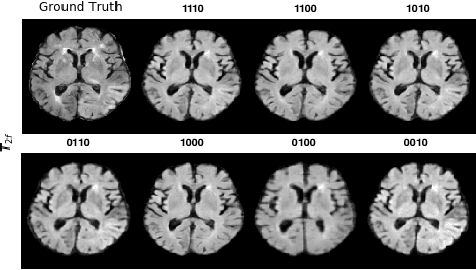

Abstract:Magnetic resonance imaging (MRI) is being increasingly utilized to assess, diagnose, and plan treatment for a variety of diseases. The ability to visualize tissue in varied contrasts in the form of MR pulse sequences in a single scan provides valuable insights to physicians, as well as enabling automated systems performing downstream analysis. However many issues like prohibitive scan time, image corruption, different acquisition protocols, or allergies to certain contrast materials may hinder the process of acquiring multiple sequences for a patient. This poses challenges to both physicians and automated systems since complementary information provided by the missing sequences is lost. In this paper, we propose a variant of generative adversarial network (GAN) capable of leveraging redundant information contained within multiple available sequences in order to generate one or more missing sequences for a patient scan. The proposed network is designed as a multi-input, multi-output network which combines information from all the available pulse sequences, implicitly infers which sequences are missing, and synthesizes the missing ones in a single forward pass. We demonstrate and validate our method on two brain MRI datasets each with four sequences, and show the applicability of the proposed method in simultaneously synthesizing all missing sequences in any possible scenario where either one, two, or three of the four sequences may be missing. We compare our approach with competing unimodal and multi-modal methods, and show that we outperform both quantitatively and qualitatively.